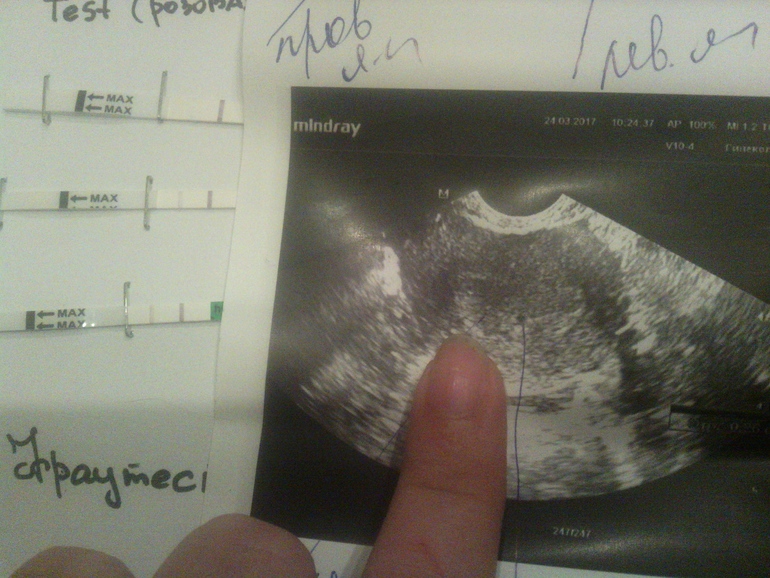

Девочки, милые, сегодня была на УЗИ, нам 3 недельки

познакомьтесь, моя миленькая точечка)))))